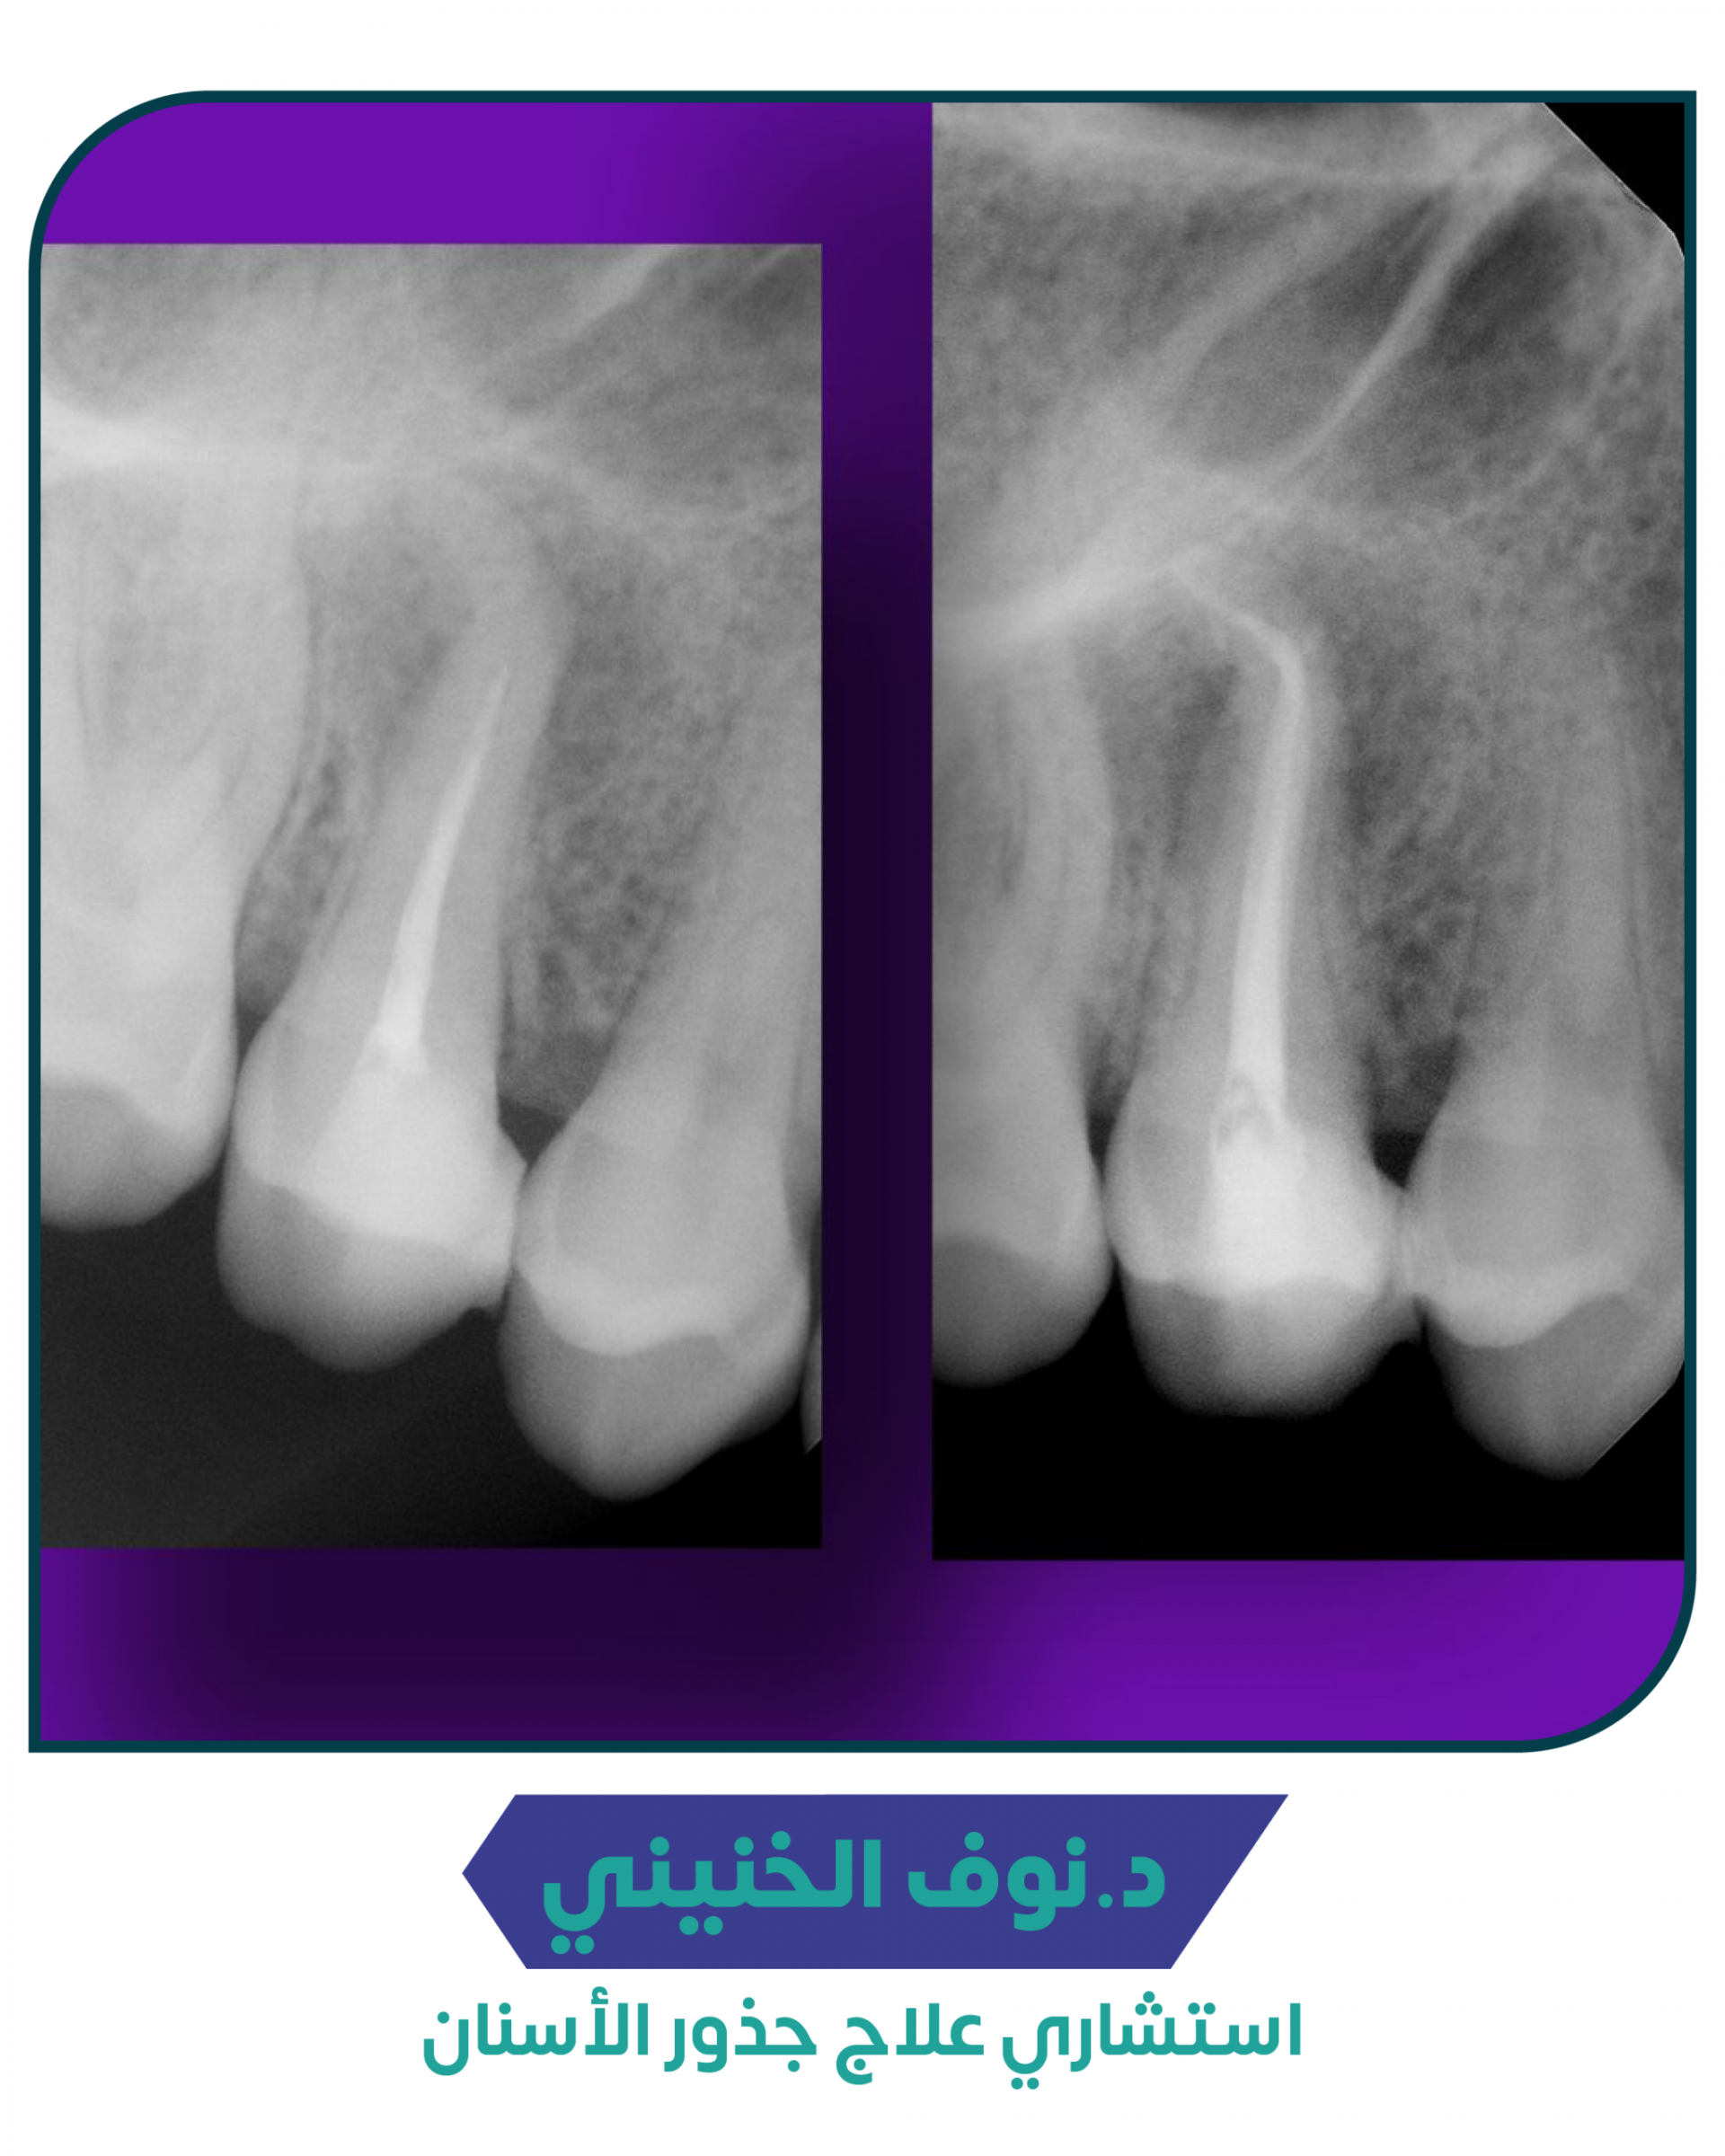

قبل وبعد --03